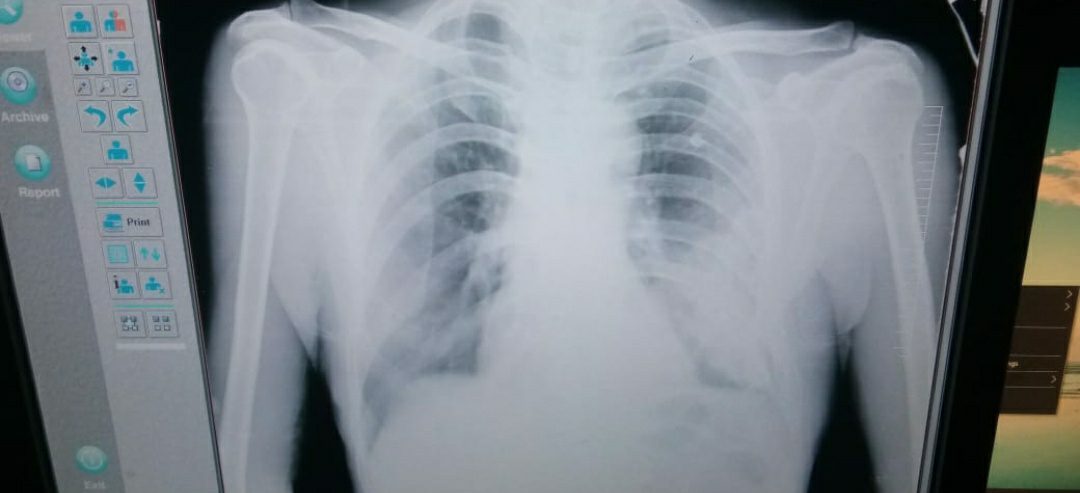

Chest x ray on 5-2-22